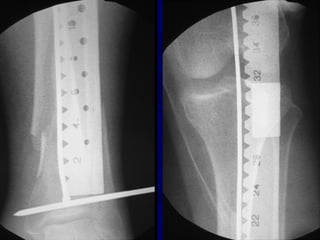

Expanded Indications • Proximal1/3 • Distal 1/3 • Increased Problems

• 53.

• Proximal Fractruesare technically more challenging • Prone to Valgus & • Pro-curvatum deformities

Technique • Screws placedon concave side of deformity.

• 56.

Blocking (Poller) Screws •Functionally narrow im canal • Increase strength and rigidity of fixation

The Use ofPoller Screws as Blocking Screws in Stabilising Tibial Fractures Treated with Small Diameter Nails • 21 patients • All healed within 3-12 months • Mean alignment 1 degree valgus, antecurvatum 2 degrees. Krettek C, et al. JBJS 81B: 963, 1999

• 58.

• Entry Sitefor Proximal fractures Critical • Reference is Lateral Tibial Spine

• 63.

Reduction of DistalTibial Fractures • Distractor • Joy Stick • Fibular Plating • Calcaneal Traction

Proximal and DistalCases Courtesy of R. Winquist M.D. Seattle, Wa.